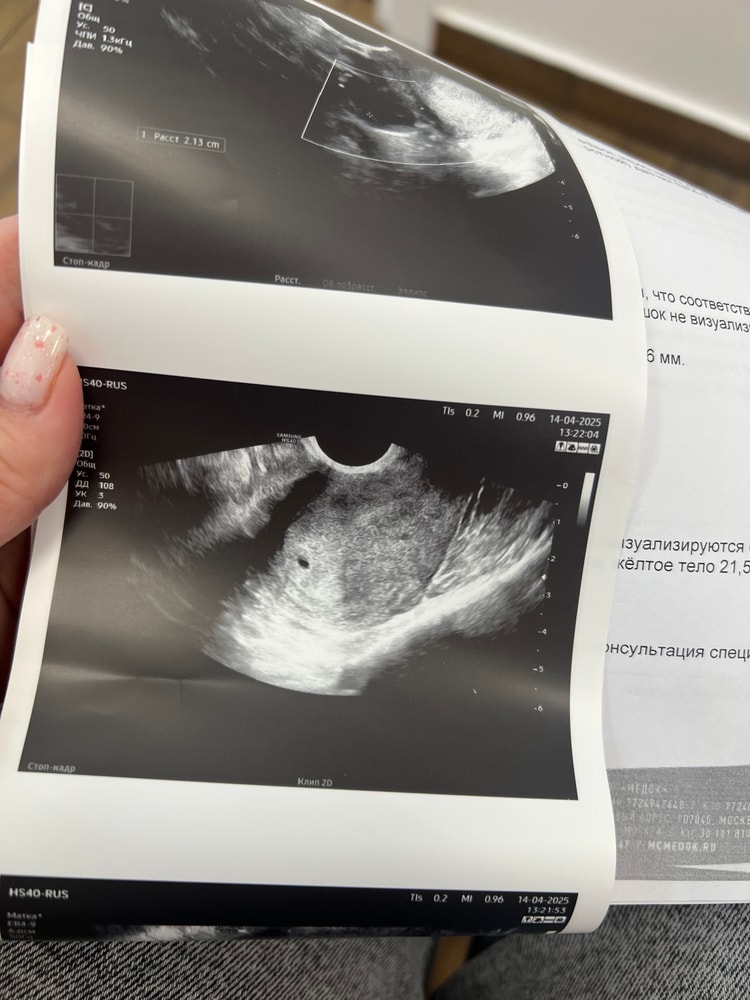

Всем привет! Была на первом узи, подтвердили маточную Б, пя 3,9 мм, срок написали 4 нед и 2 дня. Мешочка ещё не видно. А по месячным срок ровно 5 недель, 20 ДПО. Но по табличкам такой размер пя соответствует сроку по месячным.. Как так?